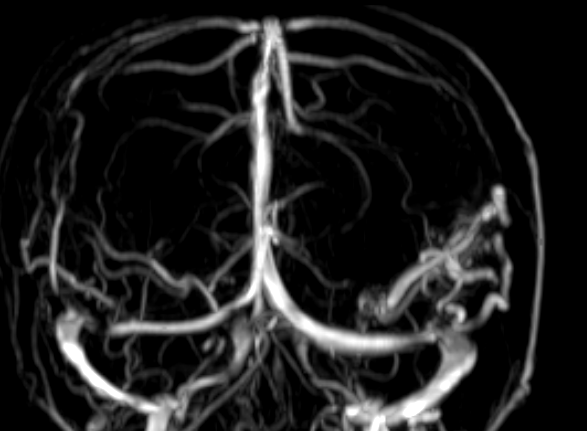

Nhân một trường hợp động kinh do dị dạng mạch máu não (AVM) Ngày 01/01/2016, Bệnh viện quân y 121 – Cục Hậu cần Quân khu 9 đã tiếp nhận bệnh nhân L.N.T, sinh năm 1990, thường trú tại Tân Thành…

Nhân một trường hợp động kinh do dị dạng mạch máu não (AVM). Ngày 01/01/2016, Bệnh viện quân y 121 – Cục Hậu cần Quân khu 9 đã tiếp nhận bệnh nhân L.N.T, sinh năm 1990, thường trú tại Tân Thành…